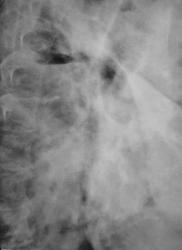

Иллюстрации 3, 4. Справа определяется почти диффузное усиление, обогащение и деформация легочного рисунка, на фоне чего дифференцируются очаговоподобные тени, округлые мелкие просветления. Тень правого корня полностью нивелирована, смещенным вправо средостением.